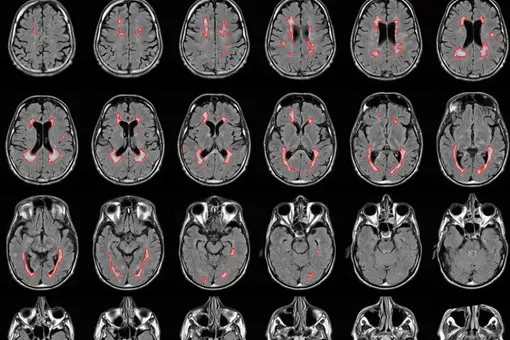

Wenn Gedächtnis, Konzentration und Wortfindung beeinträchtigt sind, nutzen wir die Hirnvolumenmessung aus der Kernspintomographie des Kopfes. Unser Neurozentrum hat seit über 15 Jahren die wissenschaftliche Expertise für diese Hirnvolumetrie. Unseres Wissens sind wir die einzige neurologische Praxis deutschlandweit, die diese Leistung anbietet.